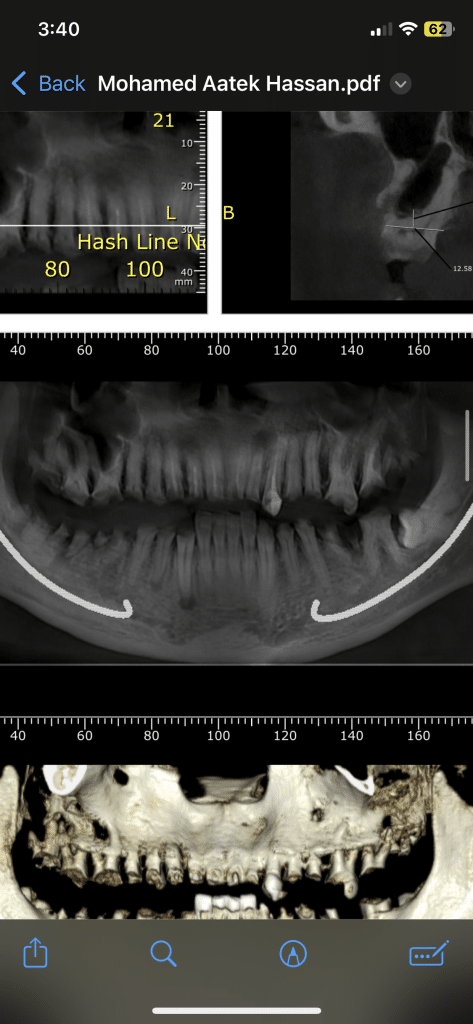

The diagnostic aid : panoramic x-ray , clinical examination .

3- extraction for lower left and right 6 molars and 7 lower left molars and immediate implanting for 6 lower left and 7 lower right ( immediate loading fro MONO Implant Swiss implants .

Upper jaw ( 3 bridges – 17-16-15-14 ) (13-12-11-21-22-23) (24-25-26-27)

Lower jaw one bridge from 37 to 47 .